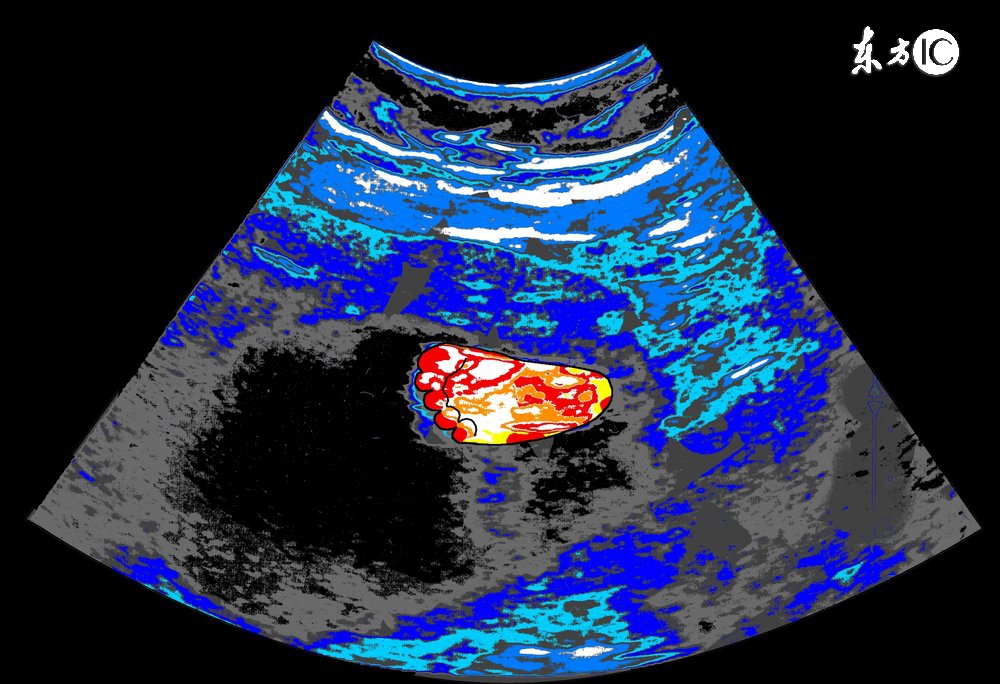

孕中期(4-6个月)

1、检查的目的:

确定胎儿大小是否与实际孕周相符,确定胎盘位置,观察羊水量,观察胎儿有无明显畸形及脏器发育状况。

2、胎儿大小:

通过测定胎头的双顶径、头围、腹围及胎儿股骨的长度来判断胎儿的生长发育情况。

3、胎盘位置:

正常胎盘附着于子宫的前壁、后壁、宫底或侧壁,如果B超显示胎盘在子宫下段,甚至胎盘下缘达到或覆盖宫颈内口处,即为前置胎盘,前置胎盘属于高危妊娠的一种,并随着怀孕月份的增大,容易发生无痛性阴道出血,引起流产或早产。

4、羊水量:

羊水量对胎儿的生长发育十分重要,羊水过多或过少,都可能预示着胎儿畸形,一般B超单上用羊水指数来表示羊水量的多少,用以评定胎宝宝的生长发育情况,正常范围值是5-18厘米。

5、脏器发育:

孕中期的B超检查,能够清晰的观察到胎宝宝的脏器发育情况,包括面部神经系统、消化系统、泌尿系统等,可以及时发现胎儿畸形,如胎儿的肢体畸形、唇腭裂畸形等,孕妈妈还须注意B超单上的胎儿脊柱检测栏,如标注为连续,则代表正常,缺损为异常提示,可能脊柱有畸形的情况。